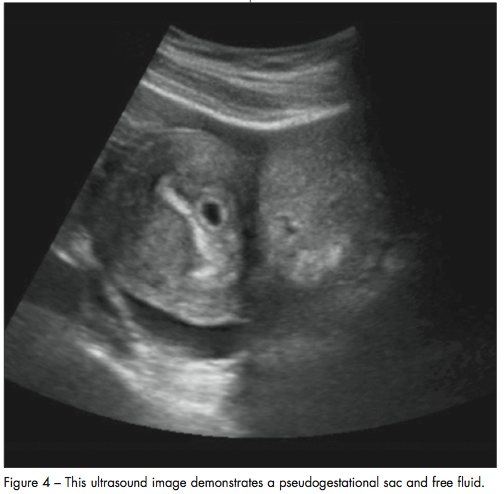

Beta-hCG above the discriminatory zone (higher than 1500 mIU/mL). The finding of a gestational sac on an ultrasound scan is suggestive but not completely diagnostic of an intrauterine pregnancy. This is because the gestational sac can be confused with a pseudogestational sac, which is an endometrial fluid collection often associated with an ectopic pregnancy.36 The pseudogestational sac is seen in 10% to 20% of ectopic pregnancies (Figure 4).42